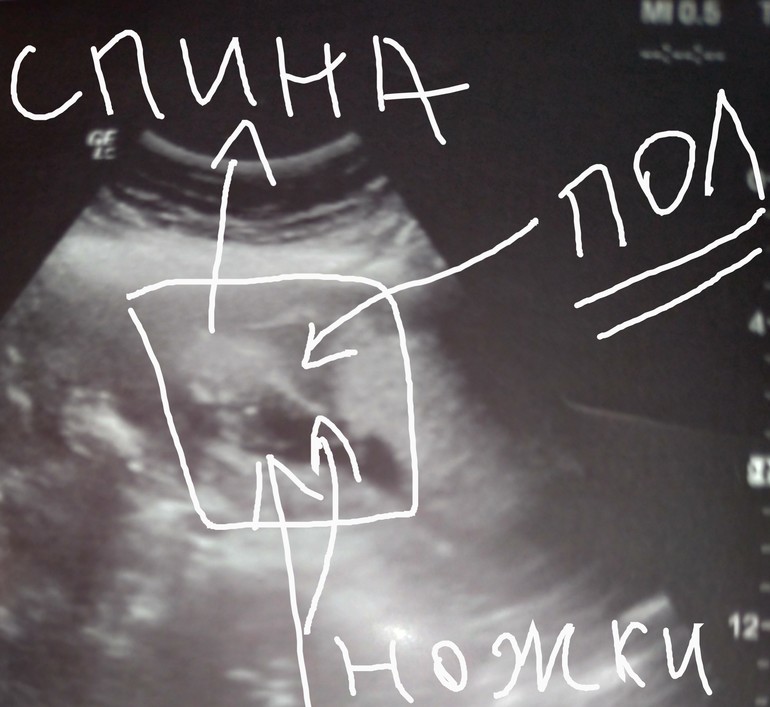

Пол малышаПривет девчонки. Вчера была на узи. Срок 16 недель и 5 дней. Пытались определить пол. В общем имеем, что имеем. Очень плохо видно тут. Так хочется хоть немного понять кто это. Может поможете кто-нибудь? Лежит спинкой, ножками ко мне. Если есть у кого какие мнения пишите. Буду рада любому.

Плохо видно.

Но я делала на этом же сроке, там прям писюн видно было. Тут вроде ничего нет. Наверное, девочка все ж

Вообще же ничего не видно🤷♀️. Узист пол не сказал? На вашем сроке уже по идее все видно. Хотя если везде так видно, как на этом фото,то переделайте узи😅

Вот фото с интернета. Сверху девочка. Нижнее мое фото отредактированное.